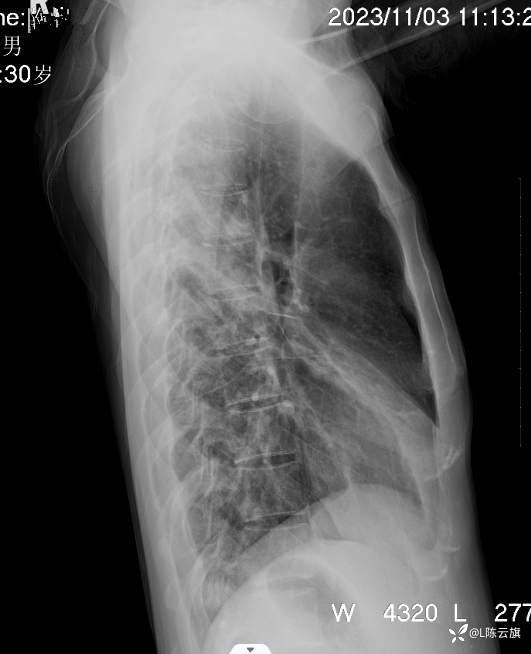

病例[每周胸片] 207 正侧位胸片 该如何诊断?(结果已公布)

患者男,30岁,精神病长期住院患者。咳嗽、咳痰二天伴发热、胸痛,体温38.5度。听诊两肺干湿啰音。